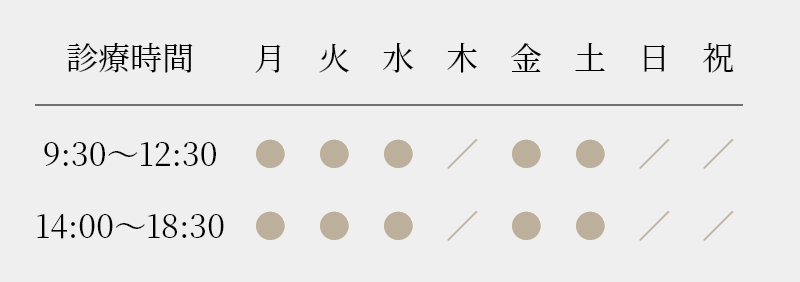

マウスピース矯正症例

症例写真

Before

治療詳細

| 主訴 | ガタガタ治したい、他院で外科矯正と言われたがしたくない |

|---|---|

| 年齢・性別 | 40代・女性 |

| 非抜歯・抜歯 | 非抜歯矯正 |

| 使用装置 | マウスピース型矯正装置 (インビザライン) 治療期間2年半 |

| リスク及び副作用 | • 歯根吸収(歯の根が短くなる症状) • 歯肉退縮(歯肉が下がる症状) • アンキローシス(歯と歯を支える骨が癒着し歯が動かなくなる) • 歯の失活(歯の神経が壊死してしまう状態) • 顎関節症(顎の痛み、開口障害) |

| 費用(税込) | 矯正検査費用:16,500円 矯正料金:880,000円 |